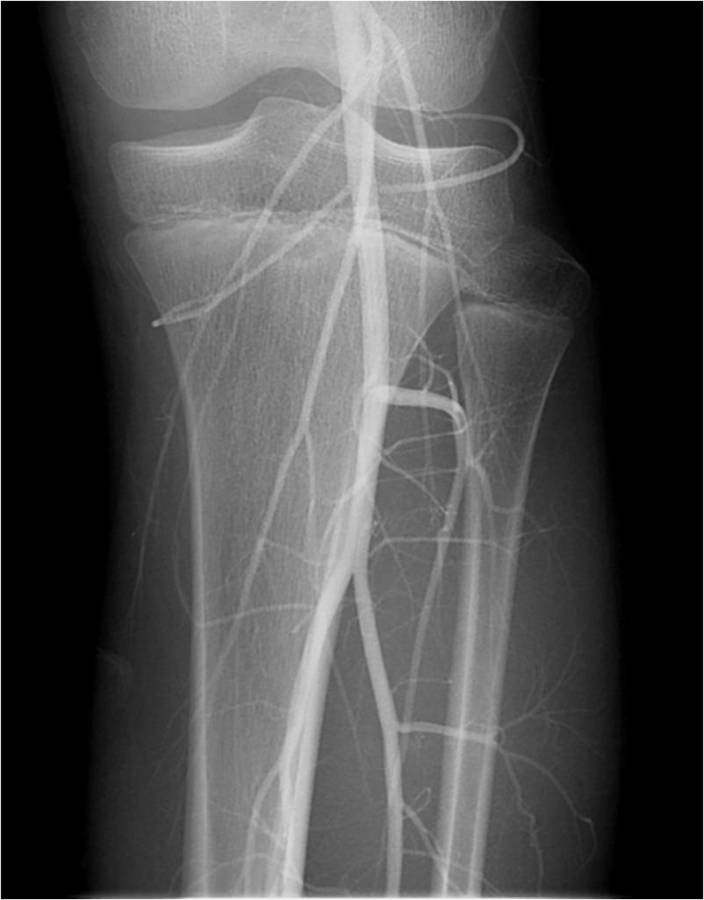

Gallery of Unlabled Radiographs from Lecture (Dr. French) - 2020

Click a thumbnail to enter the gallery display. Click the file name link at the bottom left of the gallery display to view the image at high resolution.

Labeled Plates from Lecture (Dr. French) - 2020

RadiologyLowerLimbThoraxQuestionPoolLabeled_01_2020.pdf

Click right side of plate to step forward or left side of plate to step backward.